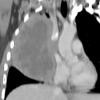

Lymphoma CT Sag

Date: 04/25/2009

Views: 3026